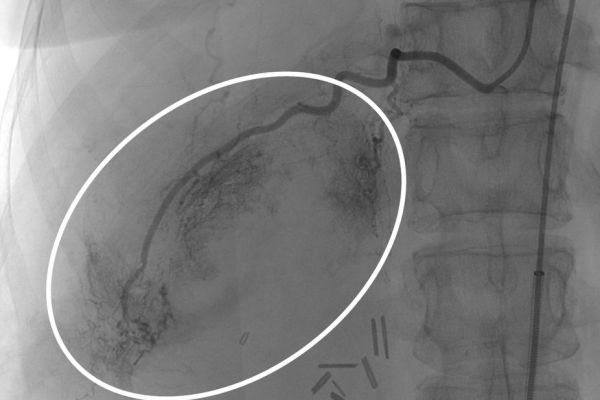

Συνοπτικά υπό την καθοδήγηση του αγγειογράφου, αναγνωρίζεταιτο παθολογικό αγγείο-αγγεία και με ειδικούς καθετήρες και μικροκαθετήρες, διοχετεύονται εμβολικά υλικάόπως μικροσφαιρίδια ή coils, ώστε να αποφραχθεί ή να μειωθεί η παθολογική αγγείωση.